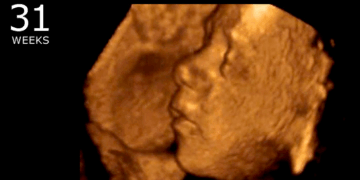

A Natrona County judge has temporarily blocked Wyoming’s Human Heartbeat Act, a law aimed at protecting unborn babies from abortion once the baby’s heartbeat is detectable. Natrona County District Judge Dan Forgey issued the temporary…